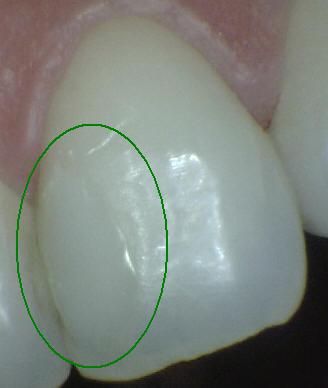

Código 2

(Caries Inicial): Lesión de

caries observada en esmalte en estado húmedo y permanece después de

secar.

- Si el margen de la

restauración está en esmalte, se debe observar el

diente húmedo. Cuando esta húmedo hay una opacidad

compatible con la desmineralización o pigmentación

que no corresponde a la aparencia clínica del

esmalte sano (Nota: la lesión sigue siendo visible

cuando se seca).

- Si el margen de restauración está en dentina: el

Código 2 corresponde a la pigmentación que no es

compatible con la aparencia clínica de la dentina o

el cemento sano.

- (Mancha blanca

/ marrón)